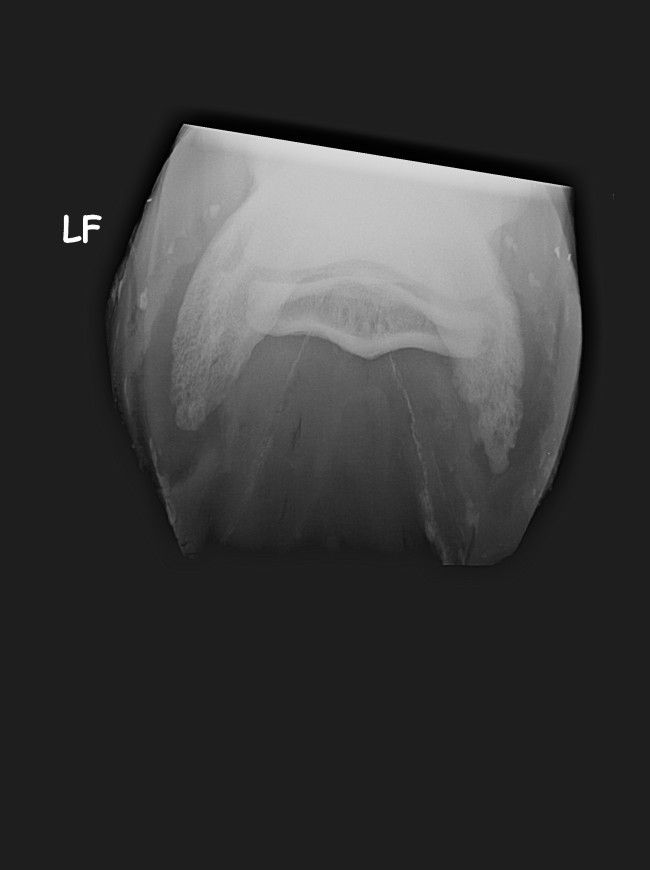

| Dire merci | de toute façon parage naturel ou non j'aurais eu ce soucis, peut être un an plus tard voir plus... Ca a juste accélérer le problème. Il a en plus une ostéite. Sinon le véto a fait exactement ce que mon véto a fait... Sauf qu'il a un oeil d'expert et pas de généraliste. Pour la "tendinite", (le tendon frottait un os qui pour finir l' abrasait ) qui est du au talon bas. Don on a fait 4 radios du pieds. On lui donne un anti inflammatoire pendant une semaine. Il a des fers à l'envers aux antérieurs. Et 6 mois de box avec sorti de 10 min par jour pendant un mois puis on rallonge de 5 min chaque semaine... Je retourne à la clinique fin septembre début octobre. |

| Dire merci | ![]() ![]() c'est le pied gauche ![]() le pied droit |